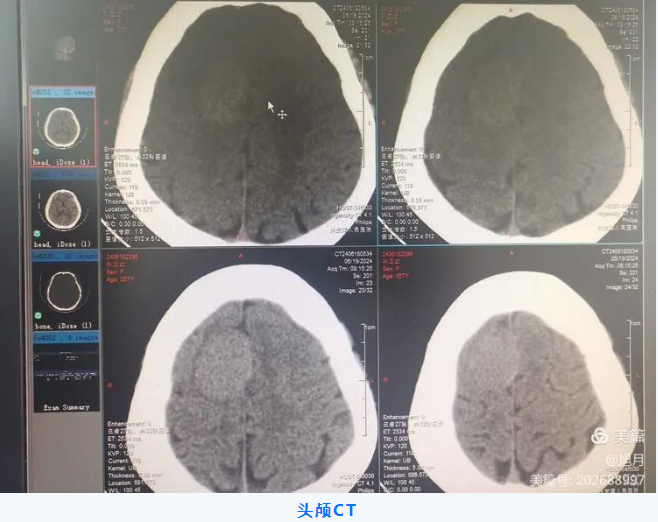

57岁女性患者,因间断头痛3月、加重10天入院,于外院查核磁提示:“大脑中线部占位性病变”,为进一步治疗来我院就诊。